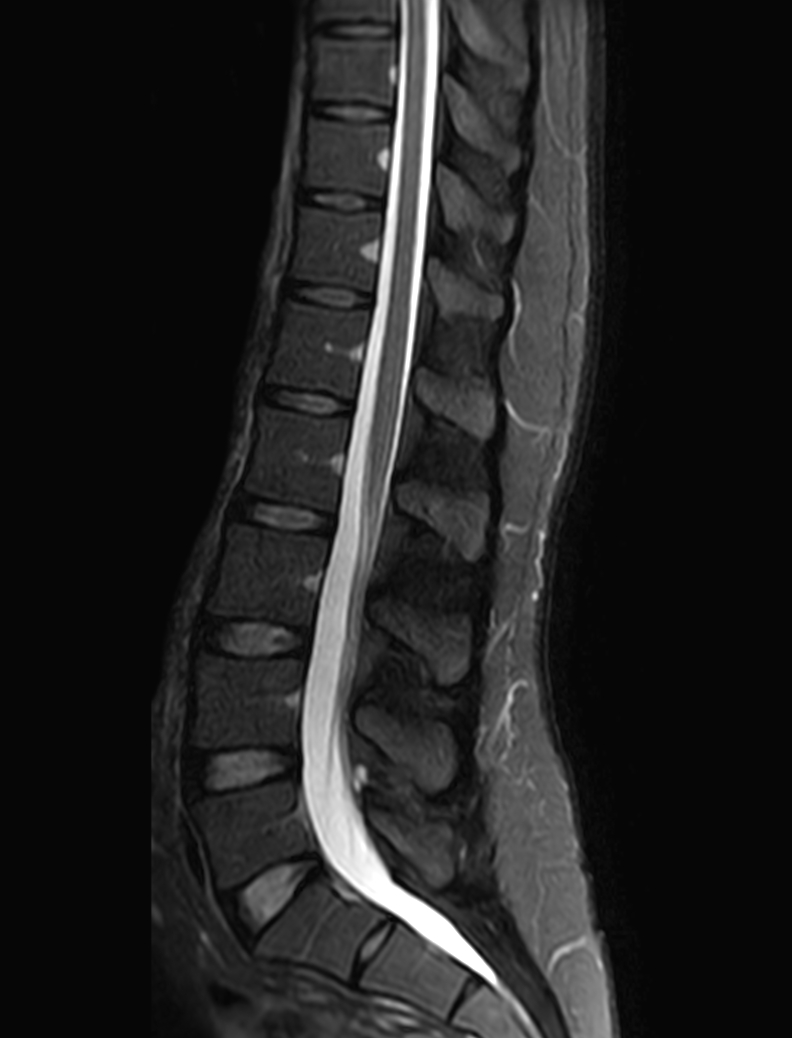

Sagittal mDIXON XD - T2w TSE (partial FatSat)